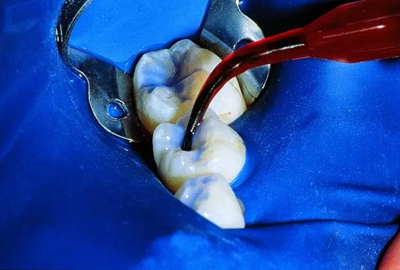

(1)酸蝕20秒,沖洗。圖示為應(yīng)用螺旋毛刷輸送頭,也可以使用藍(lán)色輸送頭。

(2)吹干,并使用PrimaDry干燥介質(zhì)。圖示應(yīng)用的是黑色FX輸送頭,也可以使用藍(lán)色輸送頭來。

(3)應(yīng)用UltraSeal XT Plus窩溝封閉劑。

(4)應(yīng)用光固化等照射。